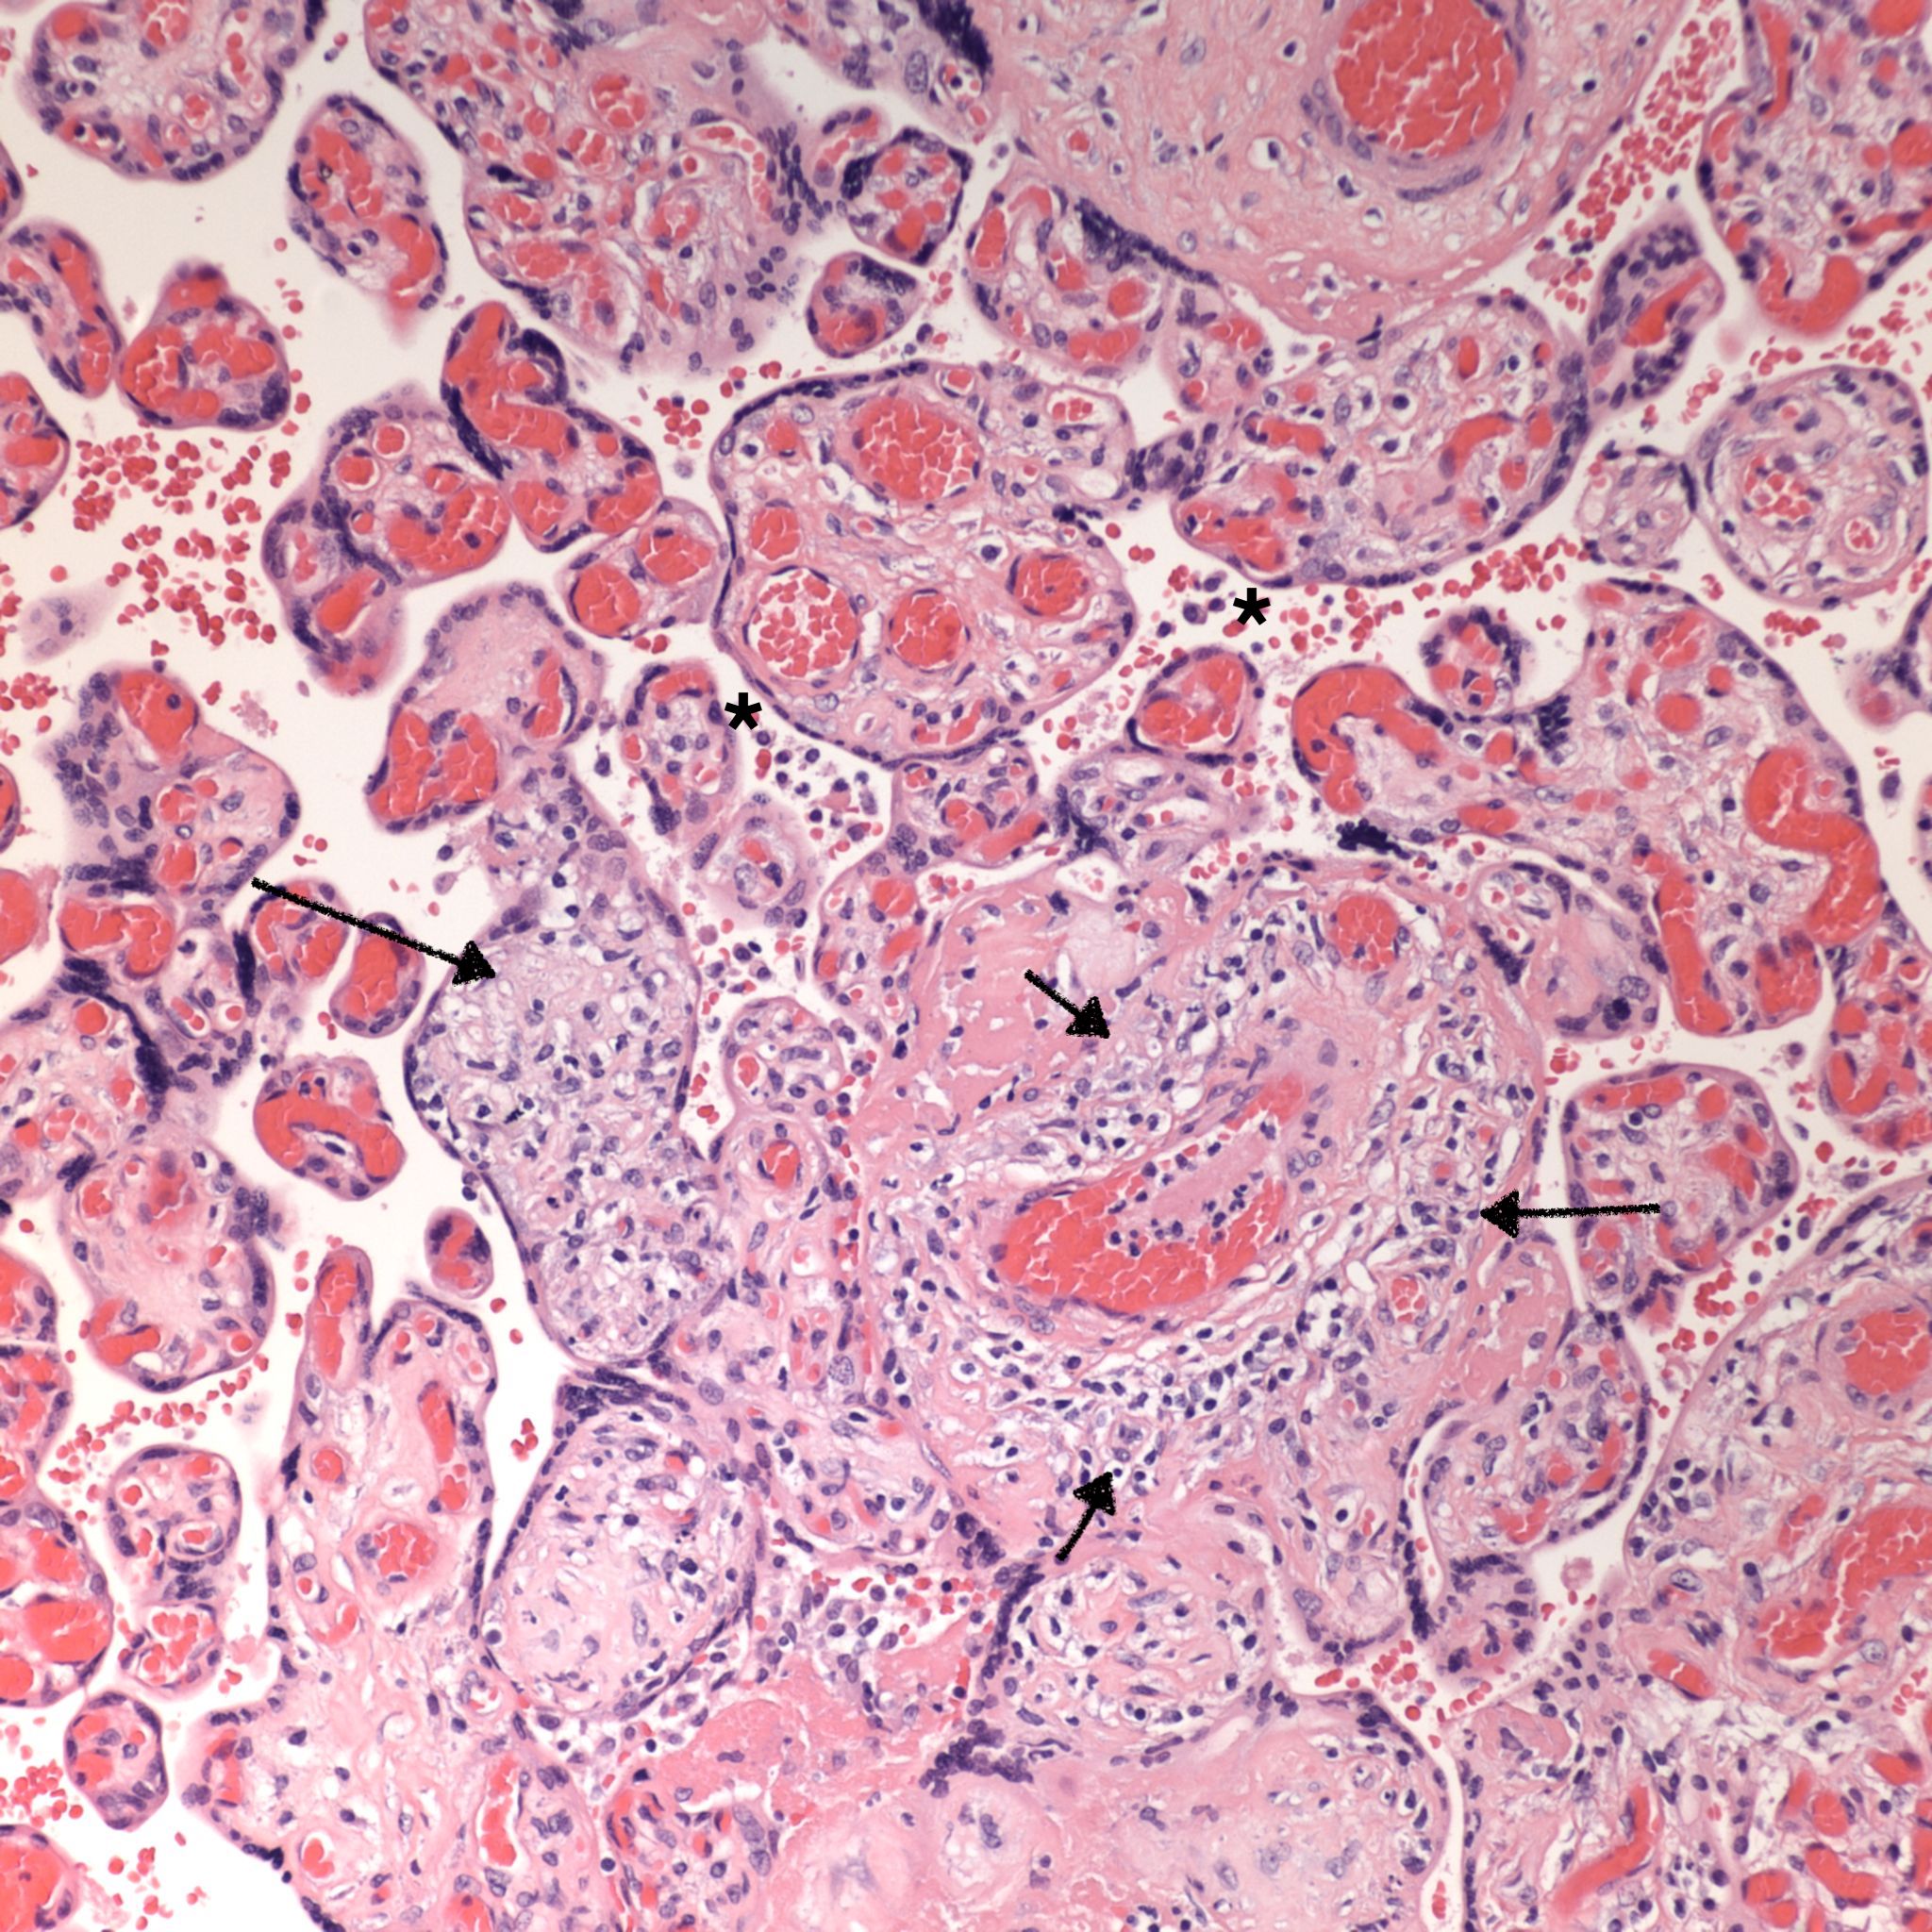

CHIV with prominent perivillous fibrinoid deposition

Perivillous fibrinoid: See entry on perivillous fibrinoid. See pathogenesis below. Some perivillous fibrinoid is a normal finding especially in the subchorionic intervillous space, along septa and adjacent to infarctions. Currently, there are no specific criteria to identify perivillous fibrinoid that is a consequence of syncytiotrophoblast injury from intervillositis. Increased perivillous fibrinoid above normal has been associated with CHIV.

5. Perivillous fibrinoid and intervillositis: Many studies mention the association of intervillositis with syncytiotrophoblast necrosis and pervillous fibrinoid deposition. The syncytiotrophoblast provides features of an endothelium with plasminogen activators. If the villous surface is injured and the underlying stroma is exposed, this is a trigger for the coagulation cascade in similar other circumstances such as in endothelial injury in blood vessels. Pervillous fibrin formation could follow, but unlike intravascular thrombi, in the placenta, the process demonstrates a mix of the underlying cytotrophoblast cells and their presumed secretions of annexins, etc. These are the same substances normally secreted at cytotrophoblast interfaces with maternal tissue. This mixture is usually referred to as fibrinoid. Such syncytiotrophoblast injury and hence perivillous fibrinoid deposition can occur in other conditions. In the case, of intervillositis, as evidenced by cd4 staining, one mechanism of syncytiotrophblast injury is likely activation of the complement cascade on the microvillous surface. The increase in perivillous fibrinoid due to intervillositis needs to be measured against the expected background deposition which can vary by gestation or diseases such as preeclampsia, as well as by normal variation by location within anatomic regions of the placenta such as below the fetal surface or along maternal septa.